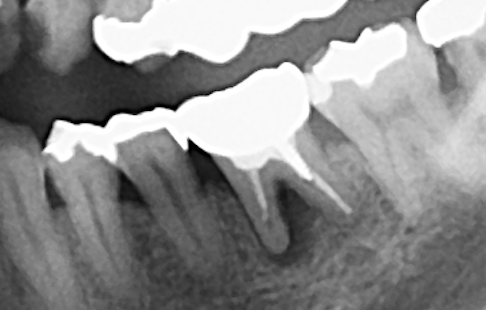

◎歯科用CT画像とレントゲン写真の違いは?

写真は同一部位のレントゲン写真とCT画像です。レントゲン写真は顎骨の形態や走行する神経の位置、歯が生えている方向把握することはできても2次元的な位置関係でしか把握できません。つまり歯や神経の位置がわかっていても実際にどのくらいの位置関係にあるのかを正確に判断することはレントゲン写真では不可能なわけです。しかし、歯科用CT画像では顎骨の形態や走行する神経の位置、歯の生えている方向、さらには骨密度の状態を3次元的に画像化する事が可能なため、より正確な診断する事ができます。